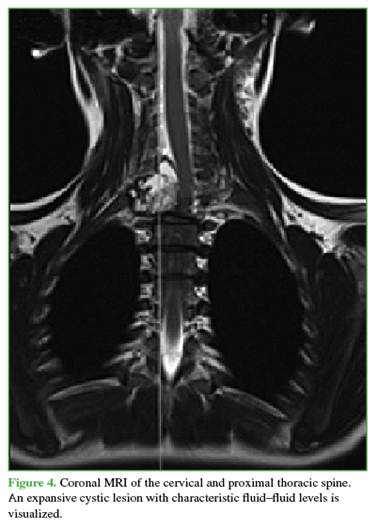

Complementary imaging revealed extensive vertebral involvement: at C7 (posterior arch), zones 4–7 and levels III and IV of the Weinstein-Boriani-Biagini (WBB) classification; at T1 (vertebral body), zones 10–3 and levels III and IV; and at T2 (right pedicle and posterior arch), zones 3–7 and levels III and IV.11 The lesions had an expansile cystic appearance (Figures 3 and 4). Due to the expansile nature of the lesion, a vertebral hemangioma was ruled out. The lesion was interpreted as an Enneking grade 3 ABC.